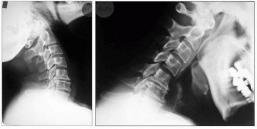

Aufnahmen von der Wirbelsäule zur Beurteilung von Veränderungen am Knochen, vor Operationen, zum Ausschluß von Knochenbrüchen und zur Verlaufskontrolle. Eine spezielle Vorbereitung der Patienten ist nicht notwendig. Moderne Röntgengeräte fertigen solche Aufnahmen mit einer geringen Strahlendosis an. Für alle, die sich genauer über die Auswirkung von Strahlen informieren wollen, empfiehlt sich ein Blick in Wikipedia.

Dies sind Röntgenaufnahmen von derselben Stelle, die in verschiedenen Körperpositionen aufgenommen werden, bei der Wirbelsäule zumeist in Vor- und Rückneigung. Sie dienen der Diagnose von Gleitwirbeln.

Die Myelograhie dient der speziellen Darstellung des Wirbelkanals im Röntgen-Bild. Dazu wird zunächst durch Lumbalpunktion ein wasserlösliches Kontrastmittel in den Wirbelkanal eingebracht. Die Untersuchung wird bei besonderen Fragestellungen betreffs raumfordernder Prozesse des Spinalkanals, oder bei der Diagnostik ausgeprägter degenerativer Veränderungen im Bereich von Hals- oder Lendenwirbelsäule eingesetzt.